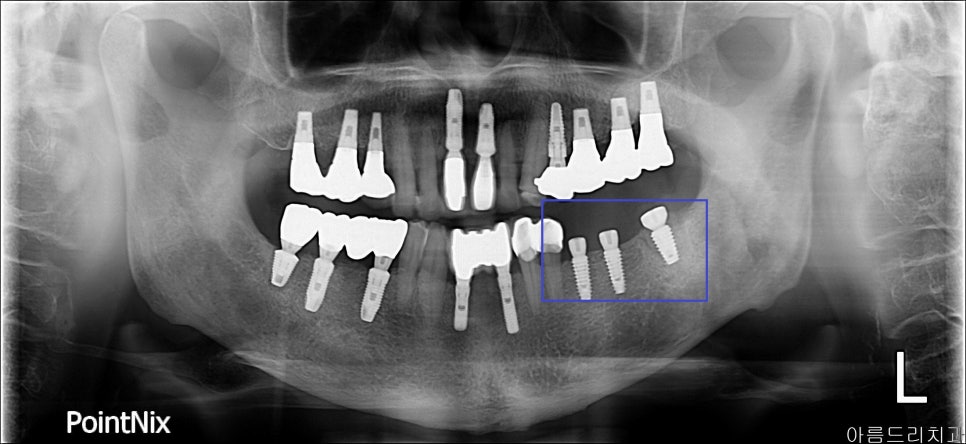

임플란트 시술 과정_아름드리 치과_ x-ray